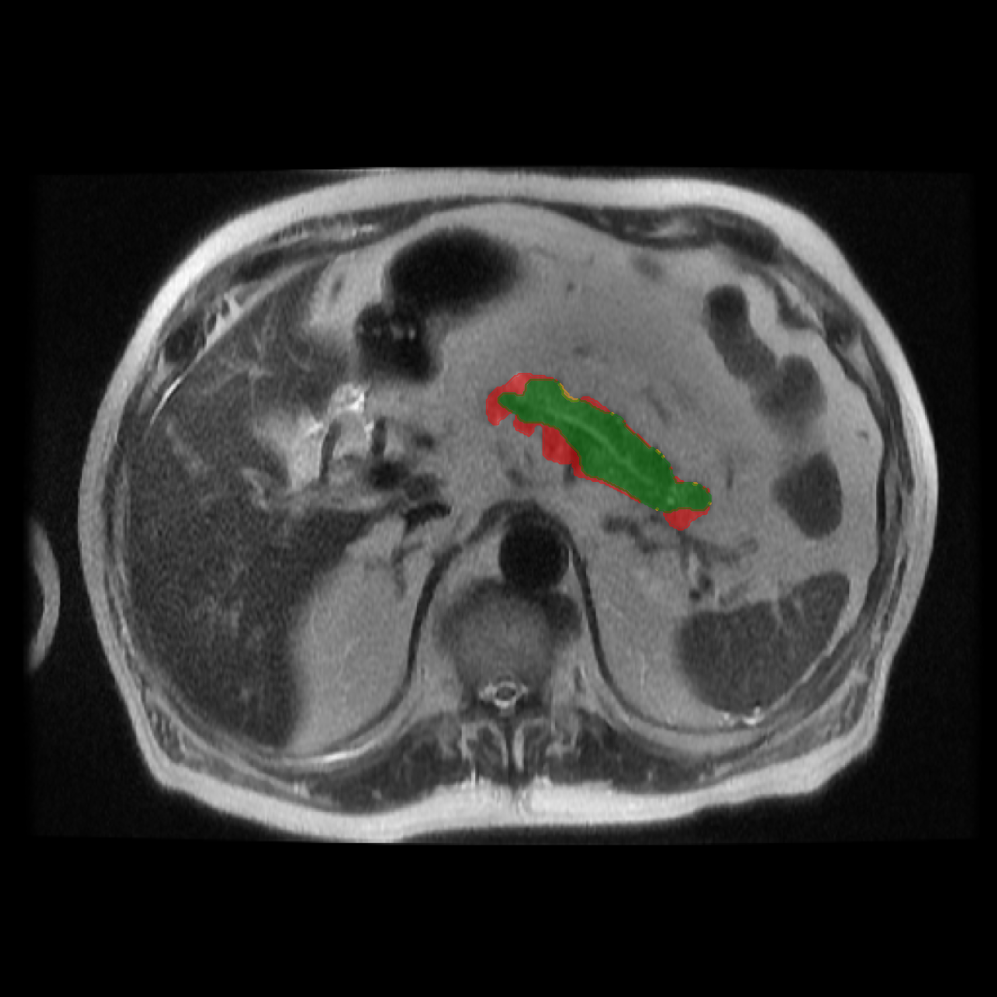

Accurate pancreas segmentation is a critical prerequisite for precise cyst analysis and classification. Recently, we developed PanSegNet [zhang2025large], a novel segmentation architecture incorporating linear self-attention layers [zhang2022dynamic] within the nnUNet framework [isensee2021nnu] to enhance global information modeling capabilities while maintaining computational efficiency (Fig. 1). PanSegNet demonstrated exceptional segmentation performance across both T1W and T2W modalities, achieving mean dice scores of 86.817.30% and 89.626.38%, respectively (Table 1, Fig. 2b-c). This performance significantly exceeded that of Swin-UNETR [hatamizadeh2021swin], one of the most used state-of-the-art transformer-based medical segmentation models, which achieved dice scores of 79.091.40% and 76.290.66% for T1W and T2W, respectively (). In this study, we integrated PanSegNet into our Cyst-X engine along with a classifier for risk prediction. In Section 2.2, we show that the choice of segmentation model affects the classification results. The performance advantage of PanSegNet was consistent across all seven medical centers, demonstrating robust generalization despite variations in imaging protocols and equipment (Table 1). This cross-institutional reliability is particularly important for clinical applications, where model performance must remain consistent regardless of imaging site or acquisition parameters.

Each patient was categorized into one of these three ground truth classes: no risk/control, IPMN low-risk, or IPMN high-risk. To evaluate variability in image acquisition, we applied uniform manifold approximation and projection (UMAP) to image quality indicators, revealing distinct clustering patterns by imaging center and slice thickness. This heterogeneity reflects real-world clinical variability, enhancing the dataset’s generalizability while presenting technical challenges for model development. Fig. 6 shows examples of low-grade, high-grade, and cancer developing IPMNs from the Cyst-X dataset.

4.2 Image preprocessing and segmentation

All MRI scans were converted from DICOM to NIfTI format for processing. Then, expert radiologists manually segmented the pancreas to establish ground-truth annotations. The segmentation protocol was standardized between centers using ITK-SNAP software [yushkevich2016itk], and a senior radiologist reviewed all masks to ensure quality and consistency.